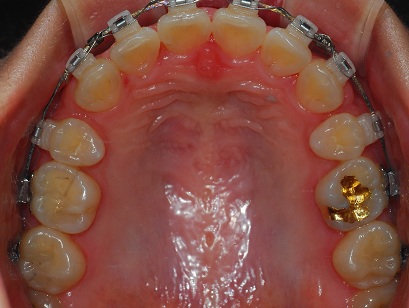

상악사진

발치공간이 거의 다 들어갓쩌?

원장선생님께서 남은기간 마무리 잘 하자 하시면서 치아 넣는 일만 남았다고 하셨어요